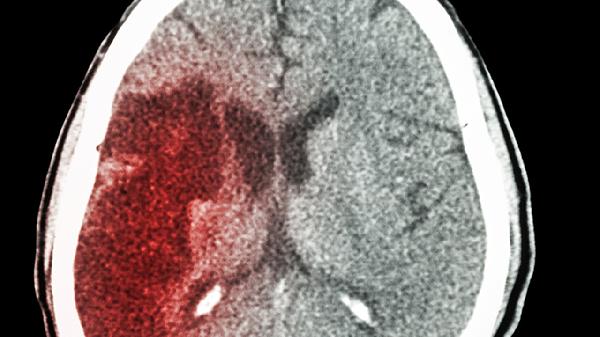

摔跤后出现脑出血有哪些明显症状

摔跤后引发脑出血的常见表现包括头痛、呕吐、意识不清、肢体无力以及瞳孔变化等。这种状况可能由外伤、高血压或脑血管结构异常等因素引起,通常会表现出上述症状。一旦发现这些情况,应尽快寻求专业医疗帮助,并按照医生指导进行治疗。

摔跤后脑出血可能导致患者出现不同程度的意识问题,从嗜睡到昏迷都有可能。这种情况的发生与出血的位置和量有关。患者还可能出现呼吸节奏异常、血压波动等现象。医生可能会采取气管插管以确保呼吸道畅通,并使用尼莫地平注射液来预防脑血管痉挛。

脑出血患者可能会出现瞳孔大小不一、对光线反应迟钝甚至消失等异常现象。这可能与脑疝形成或脑干受压有关。患者还可能伴随呼吸和循环系统的问题。医生可能会立即进行开颅手术清除血肿,并用甘露醇注射液来降低颅内压力。